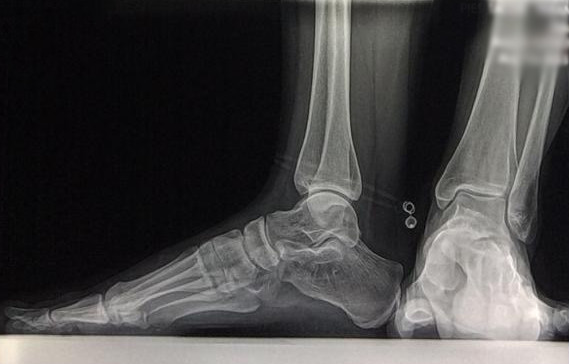

Radiología Digital como Herramienta Complementaria en el Dictamen de Bienes Muebles

Desde el descubrimiento de los rayos “X” y las placas radiográficas por Wilhelm Conrad Roentgen y su posterior difusión a través de la Asociación Físico médica de Wurzburg el 28 de diciembre de 1895, que fue la primera asociación que habló de los nuevos rayos que podían penetrar el cuerpo y fotografiar los huesos, ha habido muchos cambios tanto en la forma de obtener, procesar e incluso en la forma de visualizar, manejar y almacenar las placas radiográficas.